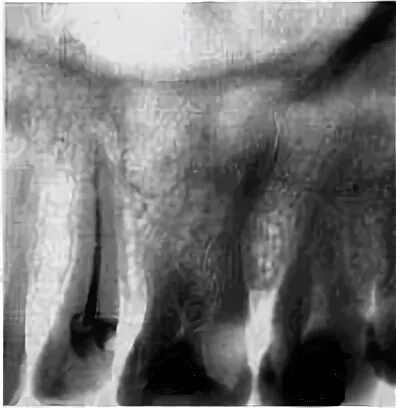

Признаки резорбции